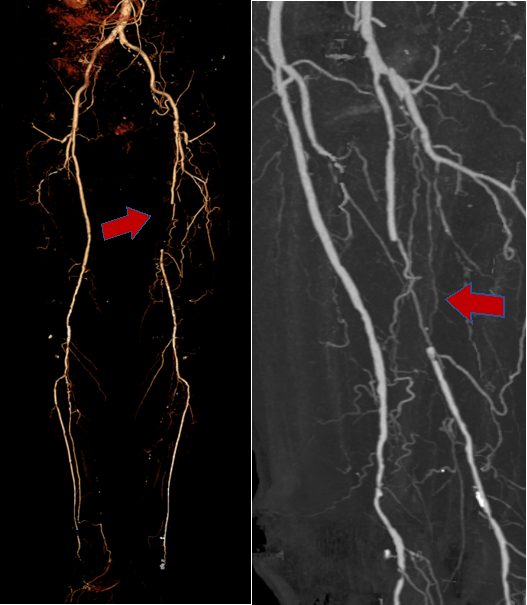

图:术前CT

图:Sterling球囊预扩张(3-150mm、5-100mm)